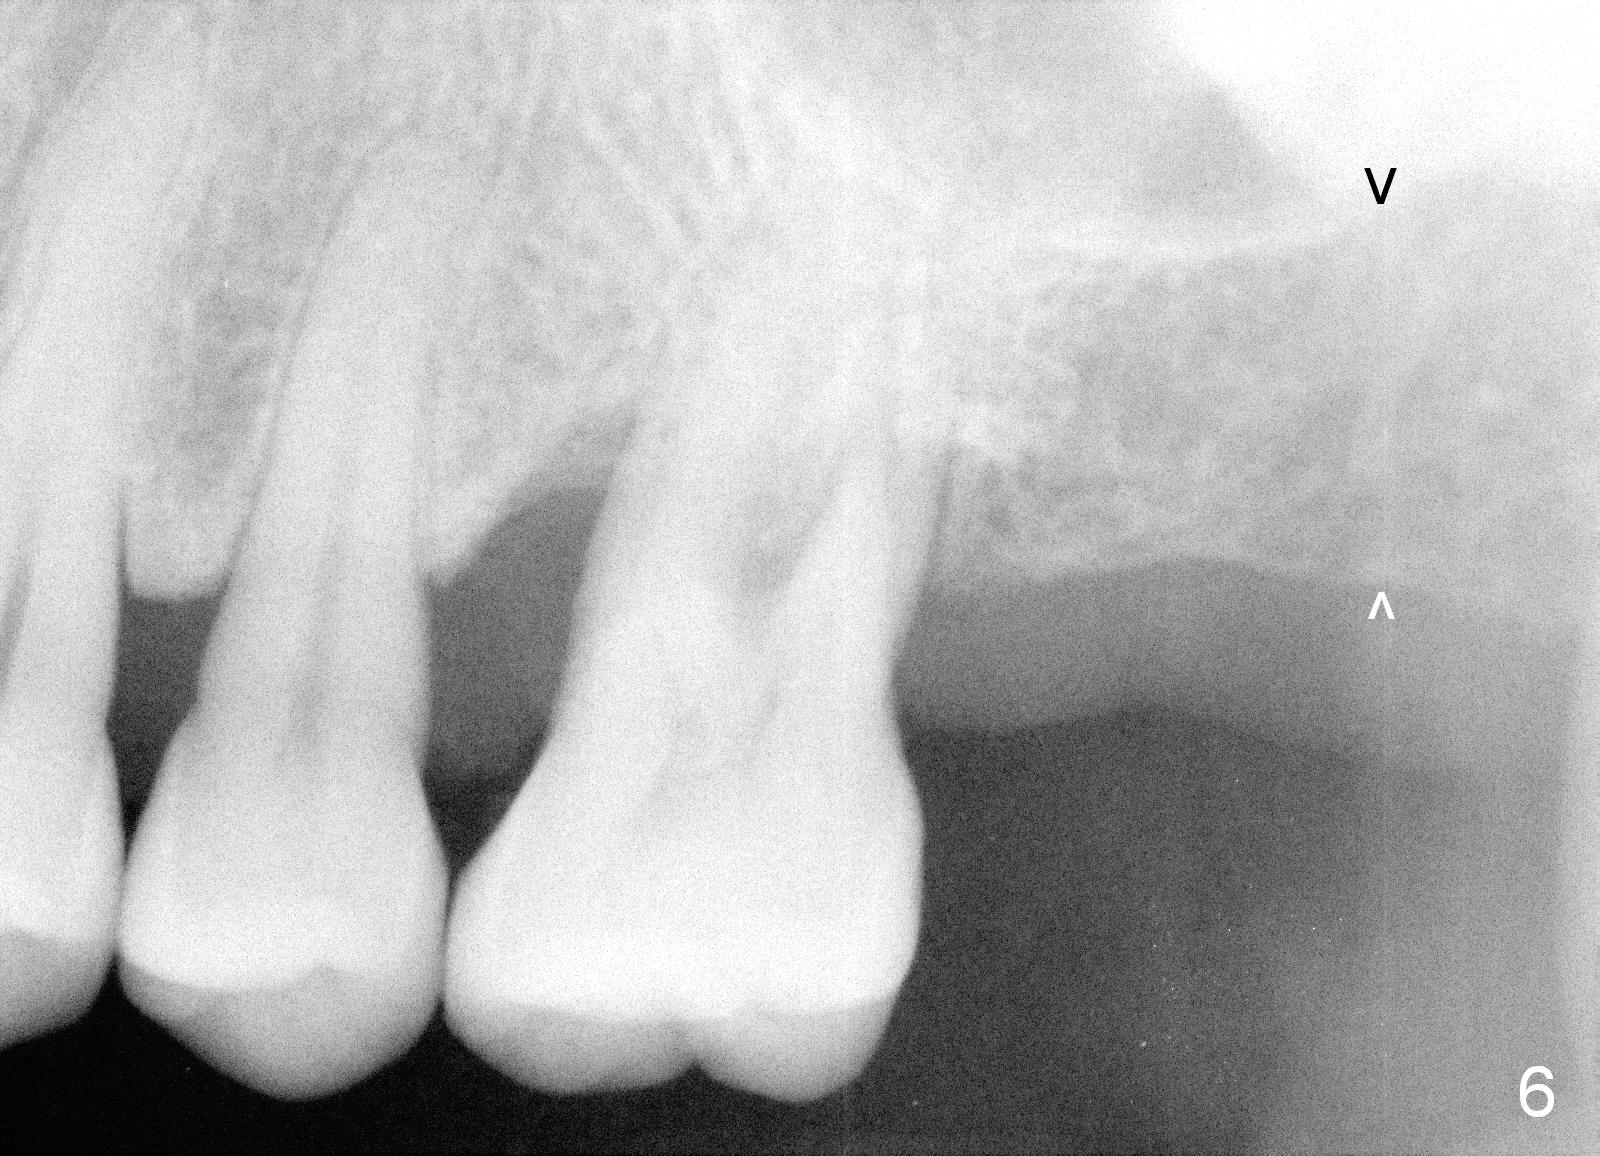

When she returns 7 years later, the tooth #2 has perio abscess with severe bone loss (Fig.3). She refuses to take antibiotic for infection control, but agrees to have immediate implant for #2 because of 1-staged surgery (Fig.5 I: 8x17 mm; A: abutment; P: bone powder (graft)). She is aware of delayed implants at the sites of #15 and 31 later. The bone height at the site of #15 reduces from 12 mm (Fig.4) to 7 mm (Fig.6) in 7 years.